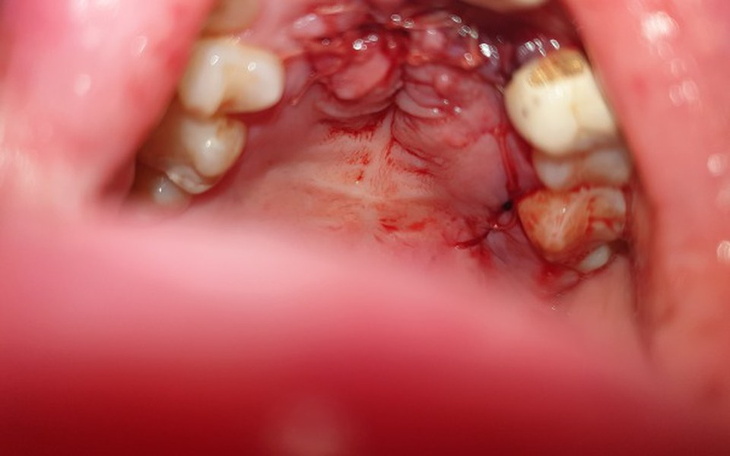

Urodziłam się z wadą wrodzoną rozszczepu podniebienia miekkiego jak i twardego, nosa oraz wargi.

Dzięki postepowi medycyny estetycznej oraz stomatologicznej w wieku 19 lat przeszłam zabieg stomatologiczny, który w pewnym stopniu zniwelował moją wadę fonetyczną oraz poprawił estetykę mojej buzi.

Szczęście nie trwało jednak długo, w związku z moją wadą tak rozleglego rozszczepu okazało się, że wczesniejszy zabieg protetyczny wymaga rekonstrukcji gdyż opada i na nowo zaburza mój zgryz, funcję mowy a co najgorsze wywołuje przeogromny ból poprzez coraz większy ścisk zębów (zdeformowana - zbyt mała szczęka).

Kolejny wyrok ... konieczna ponowna rekonstrukcja górnego łuku uzębienia.

W nadzieii odzyskania wiary w lepsze jutro musiałam poddać się operacji rekonstrukcji podniebiebia (czerwiec 2019 -załączam zdjecia) gdyż ostatnimi czasy nawet jedzenie i picie było dla mnie coraz większą udręką.

Takie na pozór zwykłe rzeczy są dla mnie codzinnym wyzwaniem...przez deformacje po rozszczepie jedzenie przedostaje się do nosa co jest mocno krępujące, na skutek ścisku uzębienia nieustanne życie w bólu a co najgorsze coraz bardziej słyszalna dysfukncja wymowy.

W związku z brakiem funduszy oraz możliwości uzbierania jak dla mnie kolosalnej kwoty 80.000 zl ( rekonstrukcja dziąsła, górnego łuku oraz uzupelnienie licznych ubytków w uzębieniu ) jestem zdana na łaskę ludzi dobrej woli.